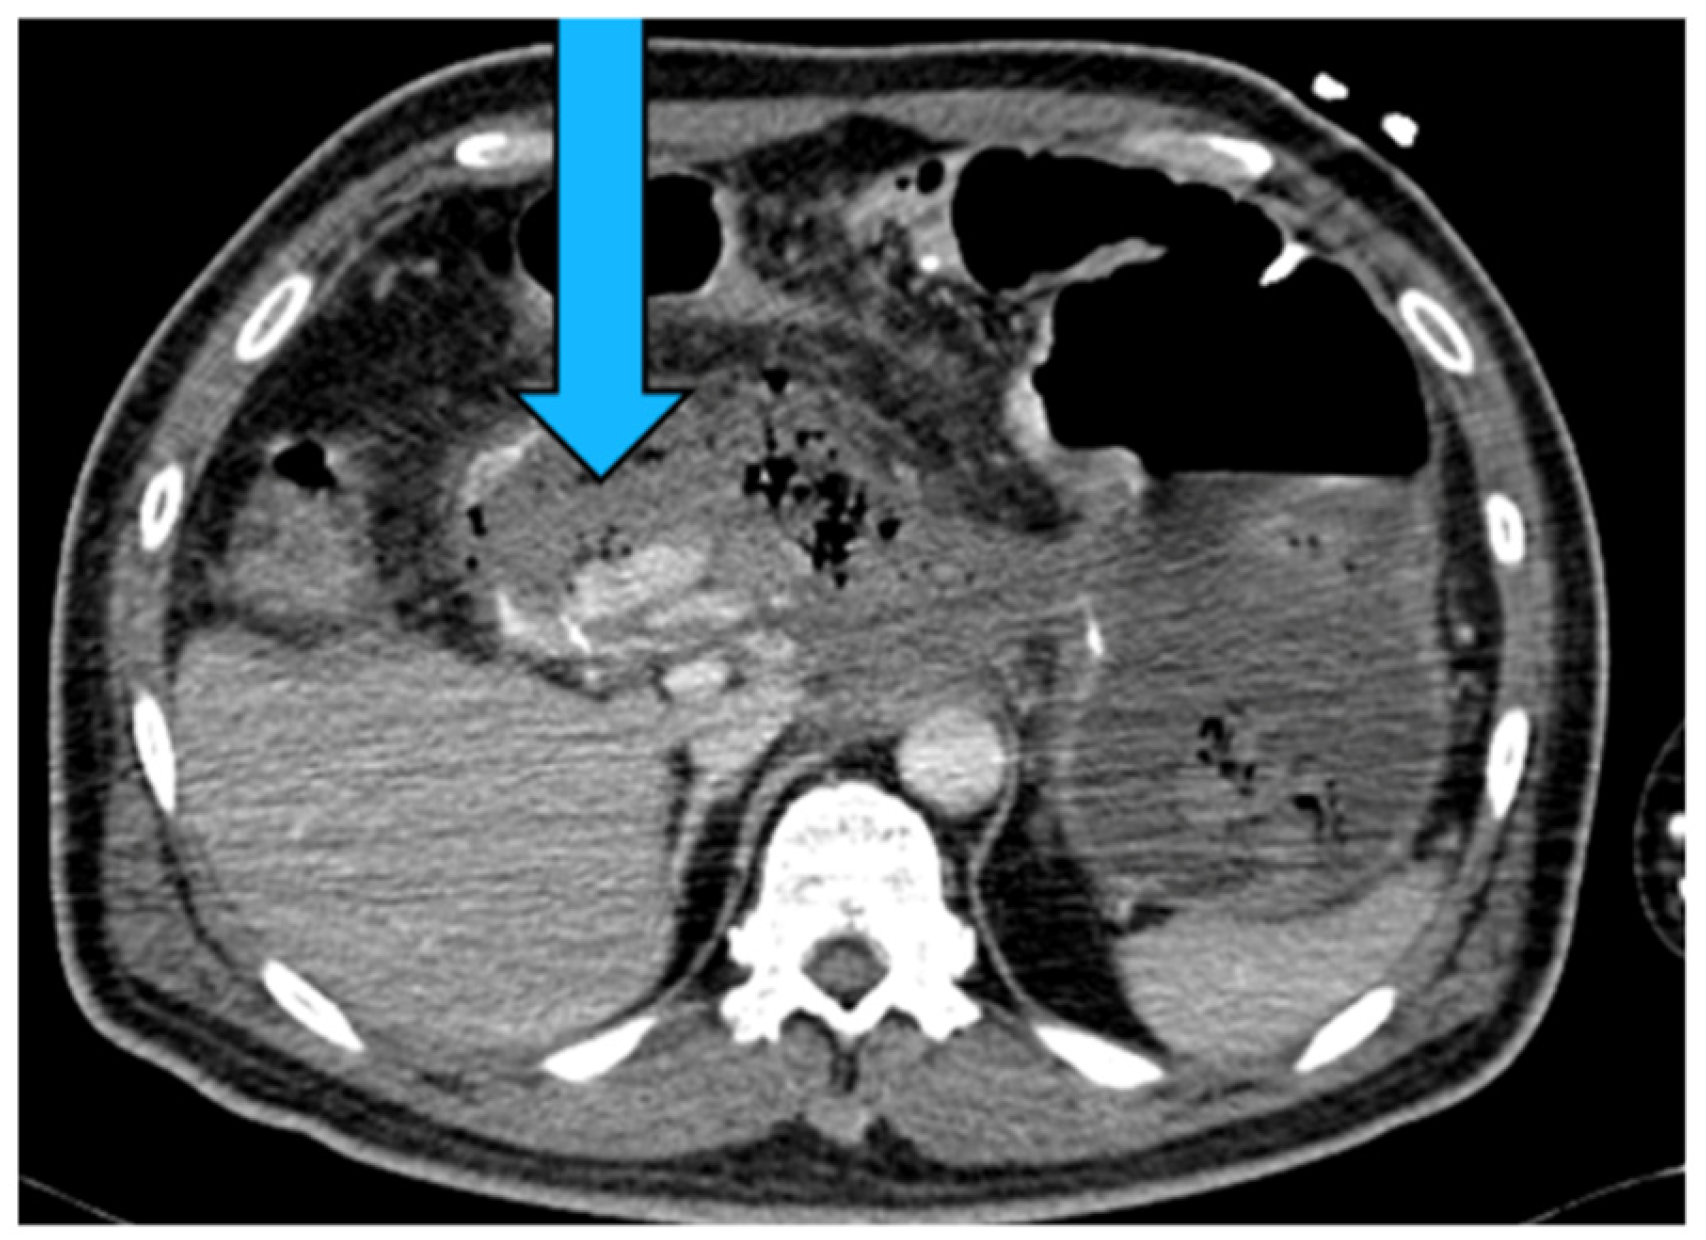

2.4. Splenic Artery

2.4.4. Diagnosis

2.4.5. Management